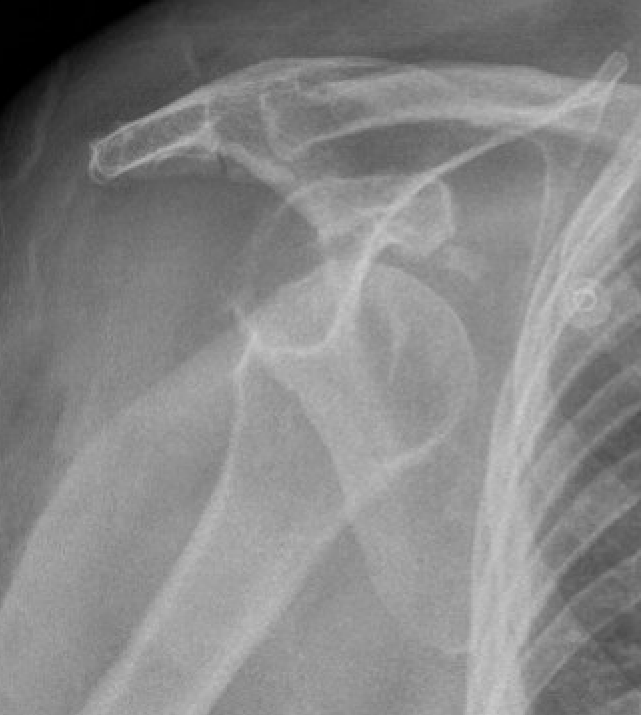

Xray

Signs of chronic shoulder dislocation